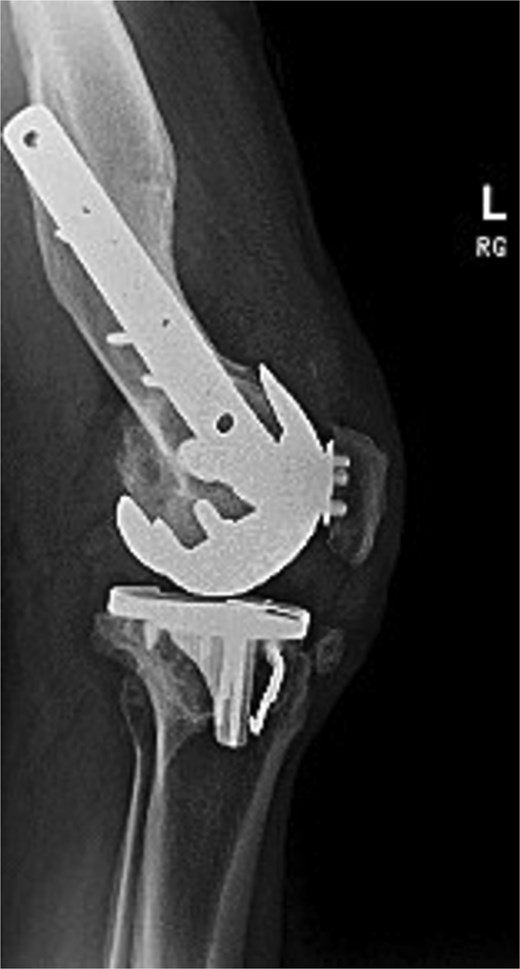

Preoperative radiographs revealed end-stage OA with osteophytes and subchondral sclerosis. Figure 1 shows the lateral view of the distal femur and knee. A healed malunion with significant recurvatum of 12° is evident, stabilized by a locking plate spanning the distal third of the femur. The plate and screws remained securely fixed, and the distal femur deformity altered the knee’s sagittal alignment with minimal impact on the coronal alignment. The AP standing long-leg radiograph (Fig. 2) demonstrated varus alignment of ~3°. The extra-articular deformity was located ~10 cm proximal to the knee joint line. No loosening of hardware or nonunion was noted. After discussing options, including staged deformity correction versus one-stage TKA, the decision was made to proceed with a single-stage TKA as the patient had a reasonable range of motion without hyperextension and a preference to avoid multiple surgeries.

Preoperative lateral radiograph of the left knee and distal femur. The pre-existing lateral plate and screws are seen along the anterior femoral cortex. A pronounced recurvatum malunion of the distal femur is evident measured at 12°. The knee joint shows severe tricompartmental osteoarthritic changes with joint space obliteration and osteophyte formation.